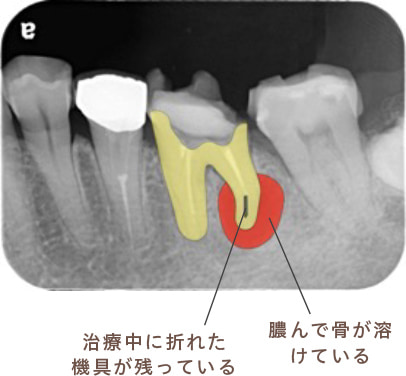

近所のかかりつけの歯科医院で、「再治療できないから奥歯を抜くしかない」と言われた。

あきらめきれず、HPで探して当院へ来院。

外すと中がドロドロに虫歯に感染していました。

折れて残っていた機具を除去

根管の中を洗浄し、無菌に近い空の状態にした。

根管の中を封鎖し終了。

治療後病気がなくなり骨が再生した